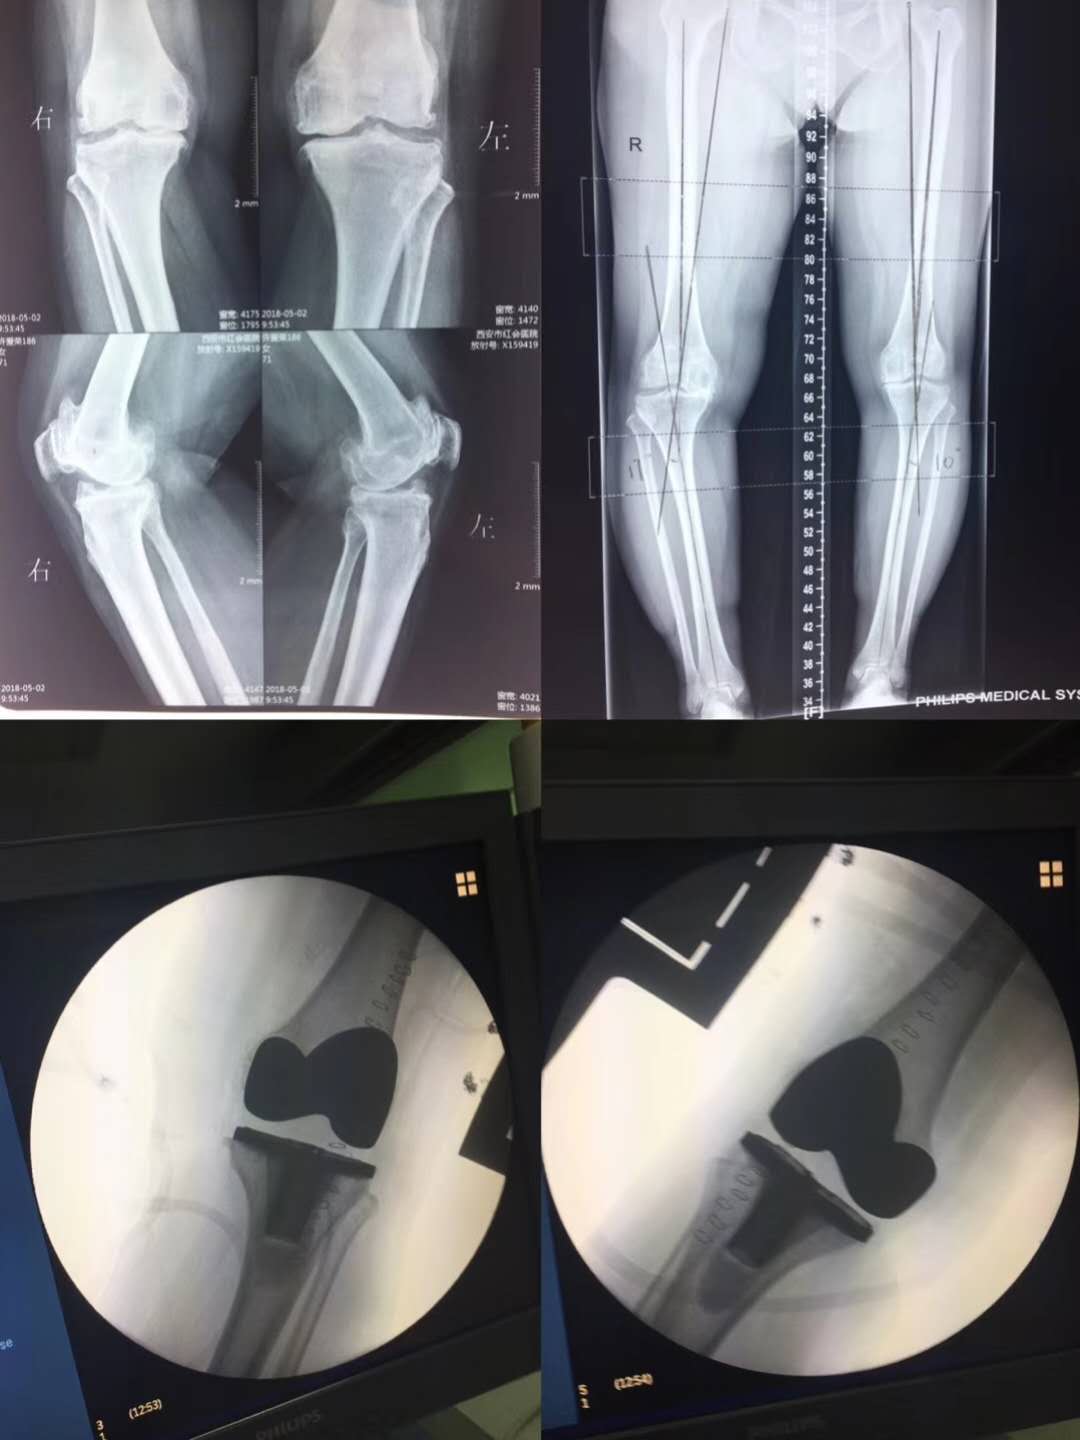

71歲的許阿姨雙膝關(guān)節(jié)疼痛12年,10年前就有醫(yī)生建議她做膝關(guān)節(jié)置換,阿姨因?yàn)楹ε戮芙^了手術(shù),近5年來疼痛越來越重,嚴(yán)重影響了她的生活。為了不給子女增加負(fù)擔(dān),她終于鼓起做手術(shù)的勇氣。

家人慕名找到骨一科宋明輝主任。宋主任對阿姨進(jìn)行詳細(xì)的查體并組織科室病例討論,決定為她施行雙膝關(guān)節(jié)置換手術(shù)。在麻醉科手術(shù)室通力協(xié)作下,手術(shù)由宋明輝主任主刀,魚紅進(jìn)副主任醫(yī)師配合順利完成。護(hù)士長高蕾和責(zé)任護(hù)士龐沖及夜班組的護(hù)士們進(jìn)行精心的術(shù)后護(hù)理,耐心細(xì)致的指導(dǎo)她進(jìn)行膝關(guān)節(jié)功能鍛煉。許阿姨的恢復(fù)狀態(tài)一天比一天好,她說:“10年前我覺得都這大年紀(jì)了,還能活幾年?做啥手術(shù)呢!不折騰了。現(xiàn)在住到醫(yī)院一看,跟你們骨一科80、90多歲做手術(shù)的老人一比,我還年輕著呢。早知道,做完手術(shù)效果這么好,我也不至于疼了這么多年才來換關(guān)節(jié)……”